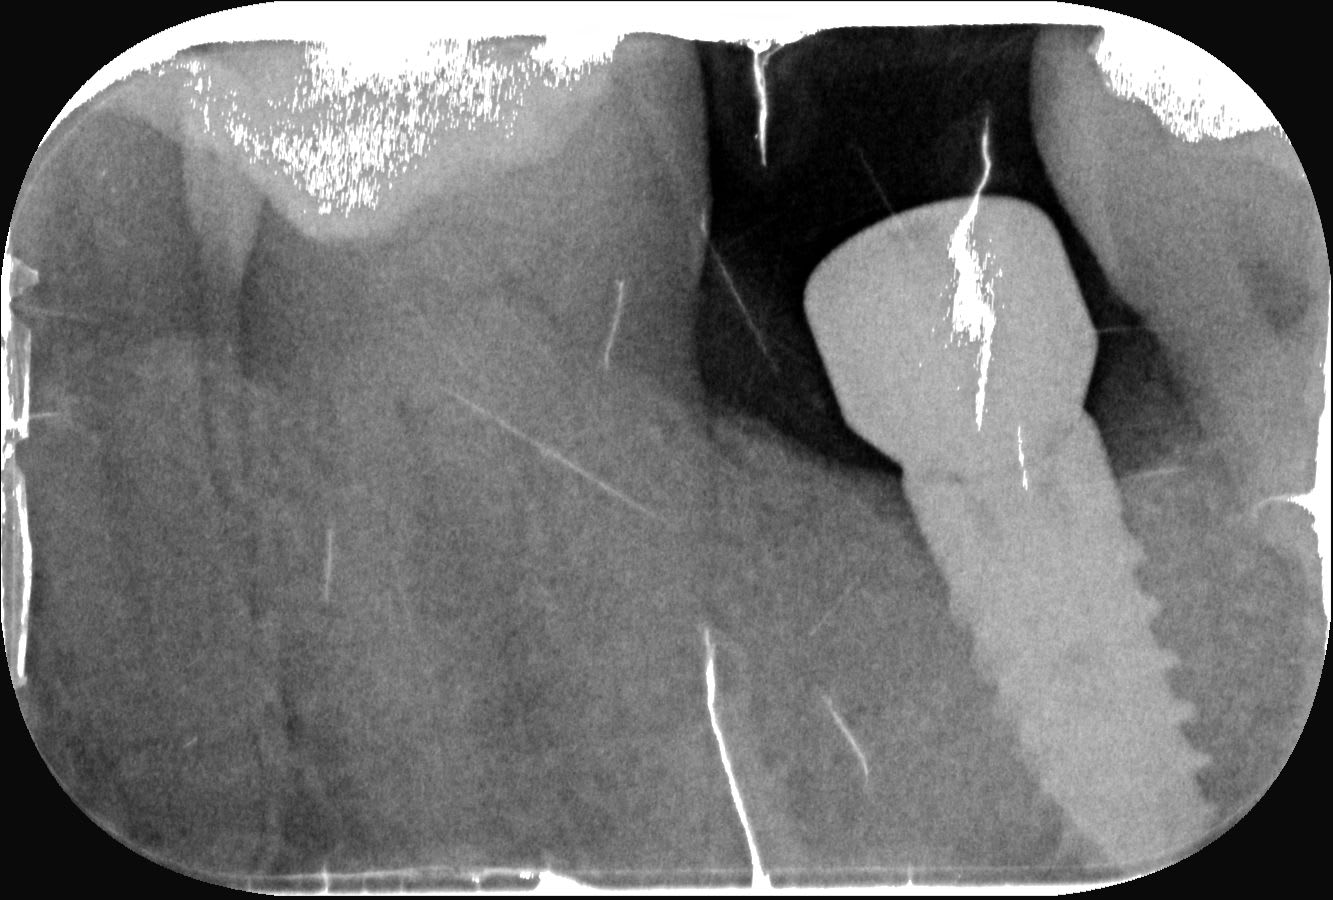

Est-ce que l'un d'entre vous, au hasard un sympathique eugenolien dont le pseudo commence par Plu et se finit par ton, serait capable d'identifier cet implant, dont la prothèse est partiellement dévissée?

L'implant a été posé aux alentours de 2010, par un praticien disparu/retraité, et aucune traça n'est dispo...

mis seven

https://www.spotimplant.com/fr/implants-dentaire/mis/seven-2

par contre de ce que je vois à la radio c'est pas dévissé....mais plutôt pilier cassé, tu as l'hexagone qui est dans le col et le reste du pilier au dessus....

Diable, j'avais repéré ce trait de fracture mais ne savais pas l'interpréter, je ne savais même pas qu'un pilier pouvait se fracturer.

Est-ce que tu sais si les implants MIS ont la même friction à l'insertion que les piliers dont j'ai l'habitude chez Zimmer?

(sous entendu, une fois l'accès réalisé et la prothèse dévissée, ai-je une chance que l'hexagone puisse être dégagé facilement, ou dois-je prévoir un démonteur de faux moignon?)